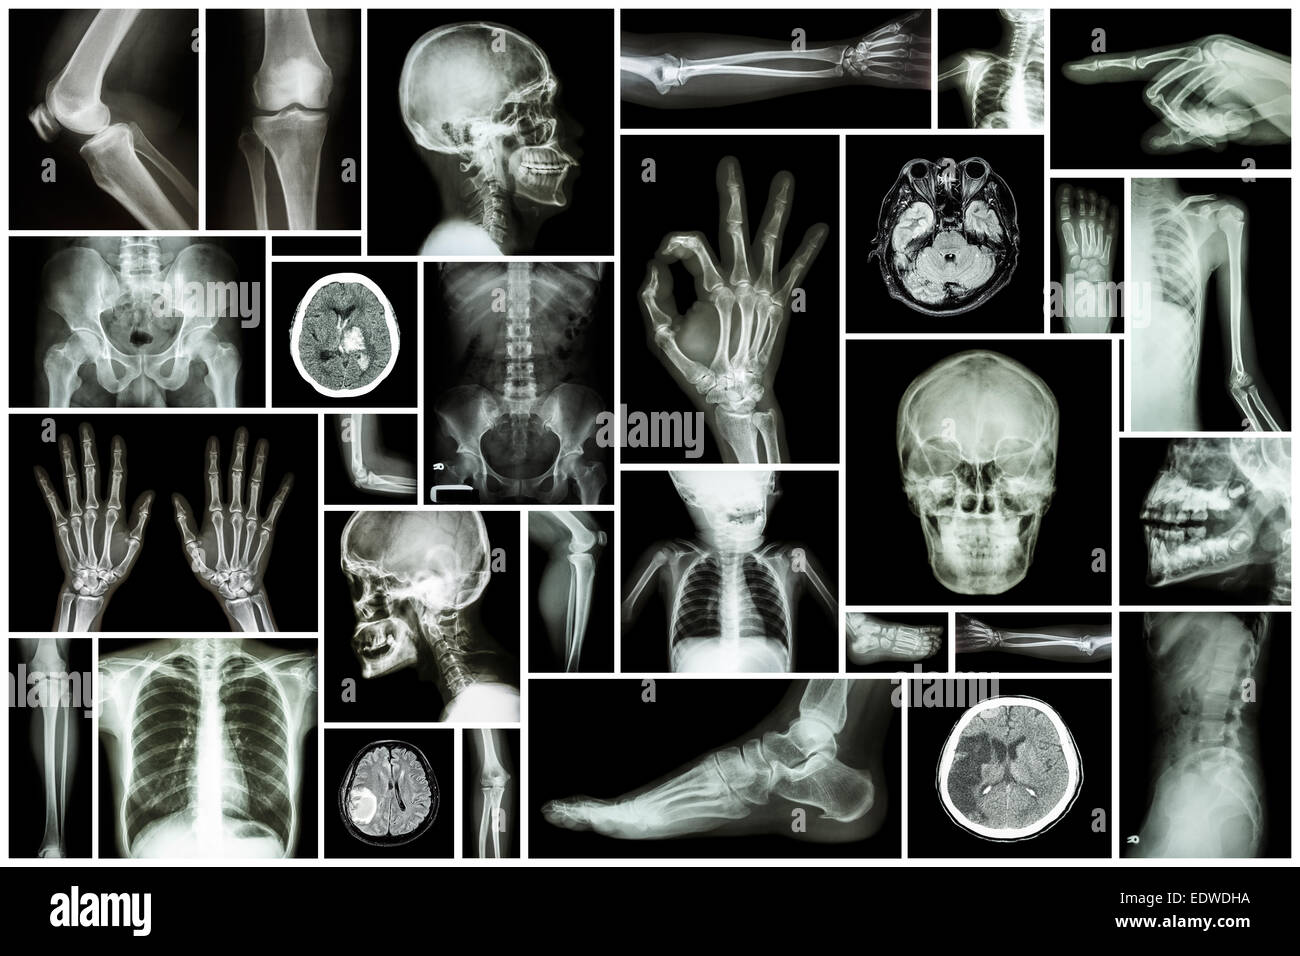

Plusieurs des droits de collecte Banque D'Imageshttps://www.alamyimages.fr/image-license-details/?v=1https://www.alamyimages.fr/photo-image-plusieurs-des-droits-de-collecte-77405487.html

Plusieurs des droits de collecte Banque D'Imageshttps://www.alamyimages.fr/image-license-details/?v=1https://www.alamyimages.fr/photo-image-plusieurs-des-droits-de-collecte-77405487.htmlRFEDX3DK–Plusieurs des droits de collecte

Plusieurs des droits de collecte Banque D'Imageshttps://www.alamyimages.fr/image-license-details/?v=1https://www.alamyimages.fr/photo-image-plusieurs-des-droits-de-collecte-77405480.html

Plusieurs des droits de collecte Banque D'Imageshttps://www.alamyimages.fr/image-license-details/?v=1https://www.alamyimages.fr/photo-image-plusieurs-des-droits-de-collecte-77405480.htmlRFEDX3DC–Plusieurs des droits de collecte

Collection X-ray partie multiples des droits de Banque D'Imageshttps://www.alamyimages.fr/image-license-details/?v=1https://www.alamyimages.fr/photo-image-collection-x-ray-partie-multiples-des-droits-de-77392127.html

Collection X-ray partie multiples des droits de Banque D'Imageshttps://www.alamyimages.fr/image-license-details/?v=1https://www.alamyimages.fr/photo-image-collection-x-ray-partie-multiples-des-droits-de-77392127.htmlRFEDWECF–Collection X-ray partie multiples des droits de

Collection X-ray partie multiples des droits de Banque D'Imageshttps://www.alamyimages.fr/image-license-details/?v=1https://www.alamyimages.fr/photo-image-collection-x-ray-partie-multiples-des-droits-de-77391478.html

Collection X-ray partie multiples des droits de Banque D'Imageshttps://www.alamyimages.fr/image-license-details/?v=1https://www.alamyimages.fr/photo-image-collection-x-ray-partie-multiples-des-droits-de-77391478.htmlRFEDWDHA–Collection X-ray partie multiples des droits de